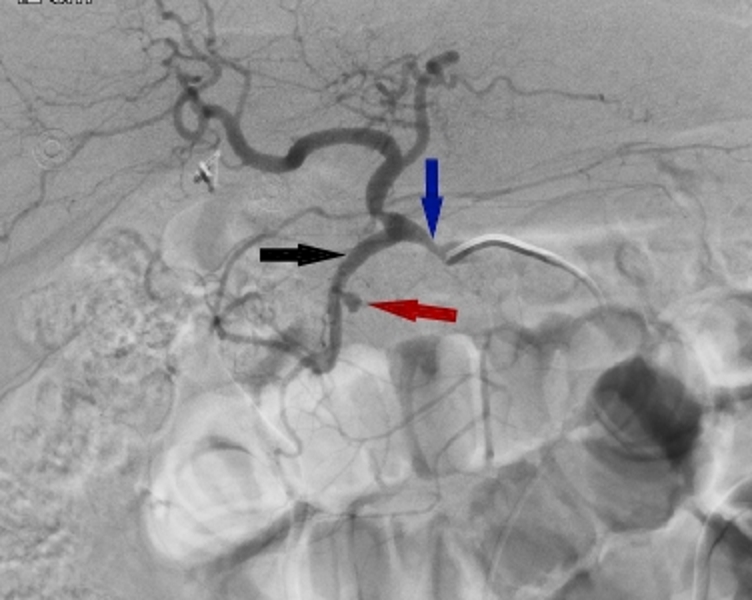

From www.researchgate.net

Typical sandwich embolization in a 73yearold man with bleeding from a Coil Embolization Of Gda Coil embolization in treatment of visceral artery aneurysms and pseudoaneurysms has achieved success rates between 75% and. The best coil position within the gda is as close to the main hepatic artery as possible to exclude perfusion of small pancreaticoduodenal side. The gastroduodenal artery (gda) is frequently embolized in cases of upper gi bleed that has failed endoscopic therapy. Additionally,. Coil Embolization Of Gda.